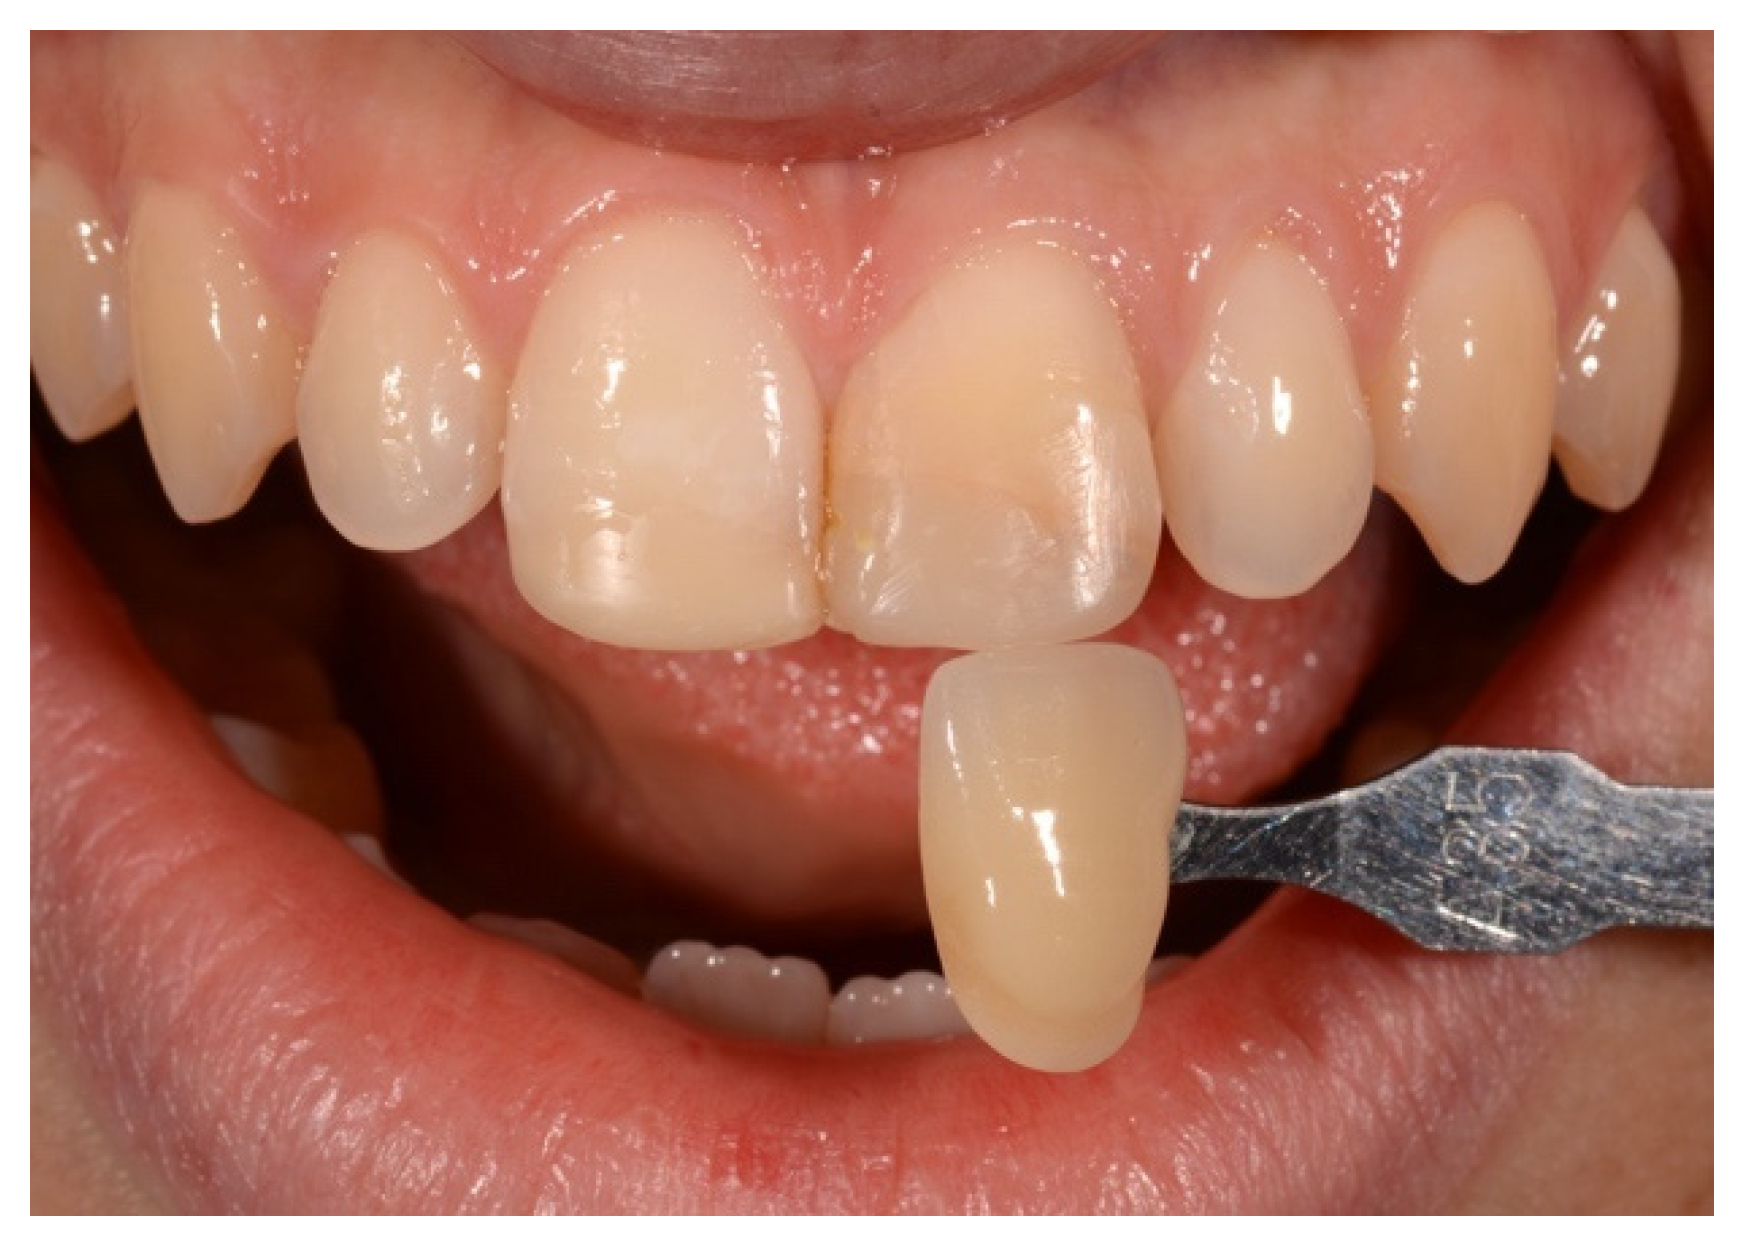

2. Case Presentation

- Paolone, G.; Orsini, G.; Manauta, J.; Devoto, W.; Putignano, A. Composite shade guides and color matching. Int. J. Esthet. Dent. 2014, 9, 164–182. [Google Scholar]